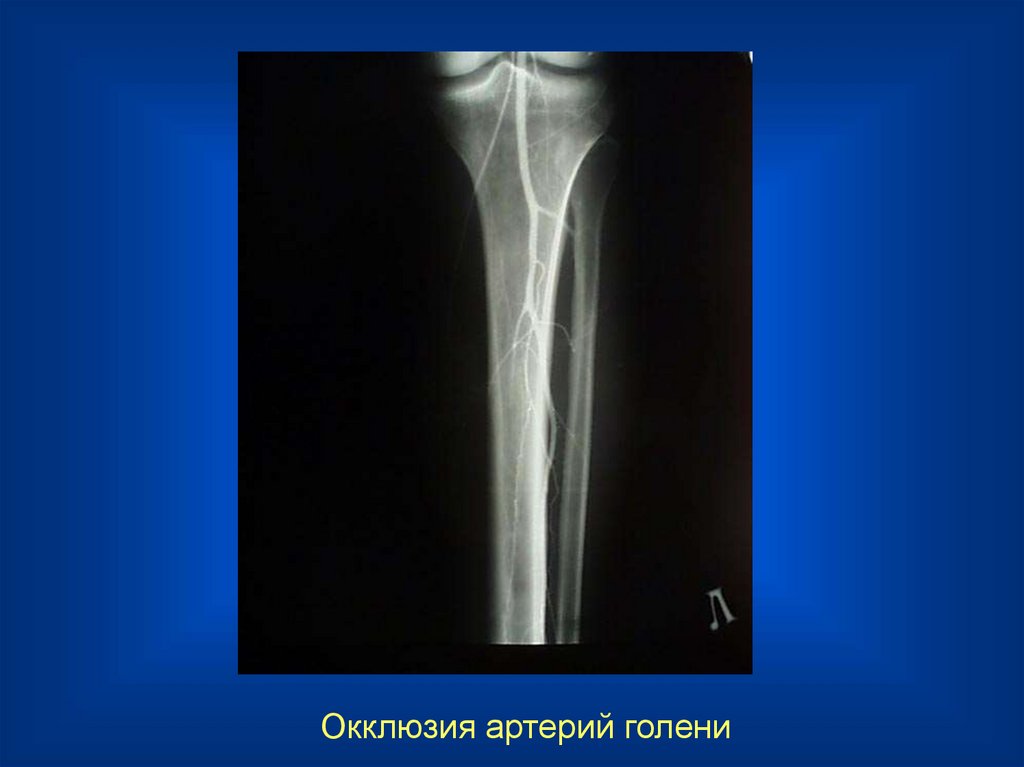

22.

Окклюзия артерий голени

23.